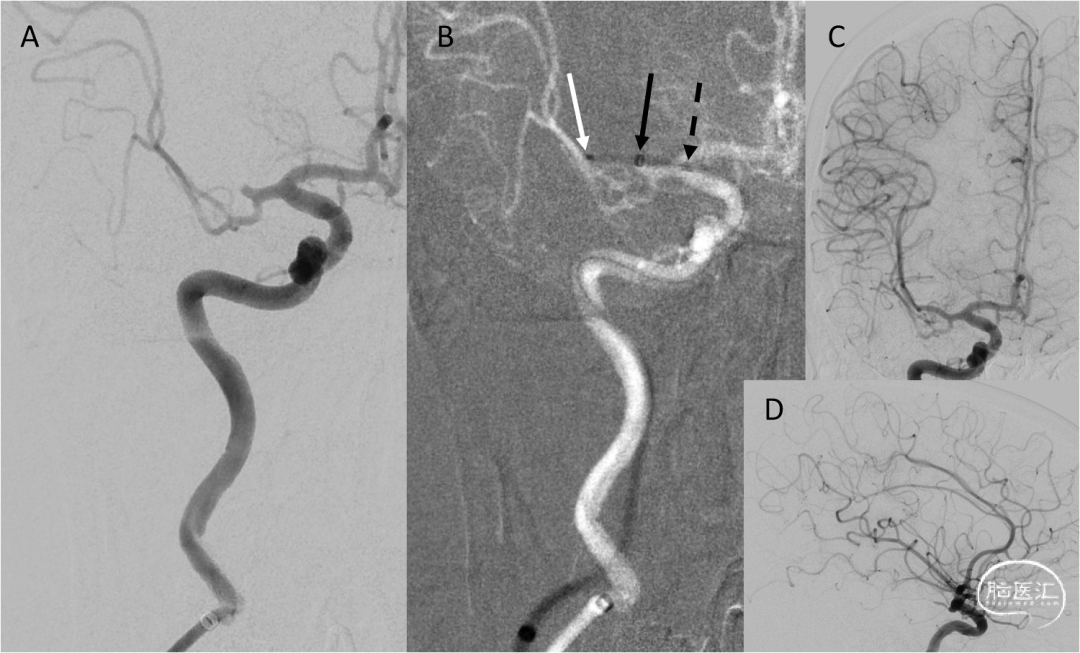

图3. 60岁患者,NIHSS 20分,ASPECTS 7分。A:右侧ICA正位造影提示右侧大脑中动脉M2闭塞。B:Tenzing 7输送(白色箭头为远端标记点,黑色虚线箭头为近端标记点)FreeClimp 70抽吸导管(黑色箭头)到位。正位(C)和侧位造影(D)显示抽吸取栓3min后实现了TICI 3级再通。